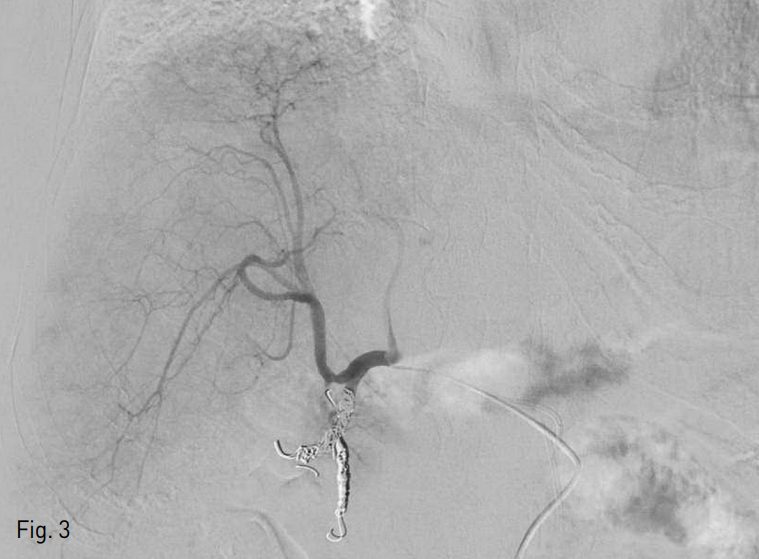

방사선색 전술 시행을 위한 사전 평가를 시행하였다. 우측 총대퇴동맥을 천자하여 4 Fr sheath 3개를 각각 삽입 후 4 Fr Yashiro catheter (Jung Sung Corp., Seoul, Korea) 3개를 사용하여 총간동맥과 좌측 전위 간동맥 (replaced left hepatic artery)이 기시하는 좌측 위동맥 (left gastric artery)에서 혈관 조영술을 시행하였다. 구역 4번의 간동맥이 공급하는 혈관이 풍부한 종양을 확인할 수 있었다 (Fig. 2). 우측 간동맥 근위부의 위이자십이지장동맥 (superior pancreaticoduodenal artery)과 위십이지장동맥 (gastroduodenal artery)을 확인하였고, 방사선색전술 시행시 위장관으로 미세구가 유입되는 것을 방지하기 위해 2.2 Fr microcatheter (Progreat, Terumo, Tokyo, Japan)로 이 동맥들을 미세선택하여 Tornado coil 4개 (3mm/2mm x 1, 4mm/2mm x 3, Cook, Bloomin gton, IN, USA), Nester coil 27H (14cm x 4mm x 2, Bloomington, IN, USA), Interlock detachable coil 27H (8mm x 20cm x 1, 6mm x 20cm x 1, Boston scientific, Natick, MA,USA)를 사용하여 색전술을 시행하였다 (Fig.3).

Fig. 3

Microembolization of the superior pancreaticoduodenal artery and gastroduodenal artery was done with 8 microcoils.